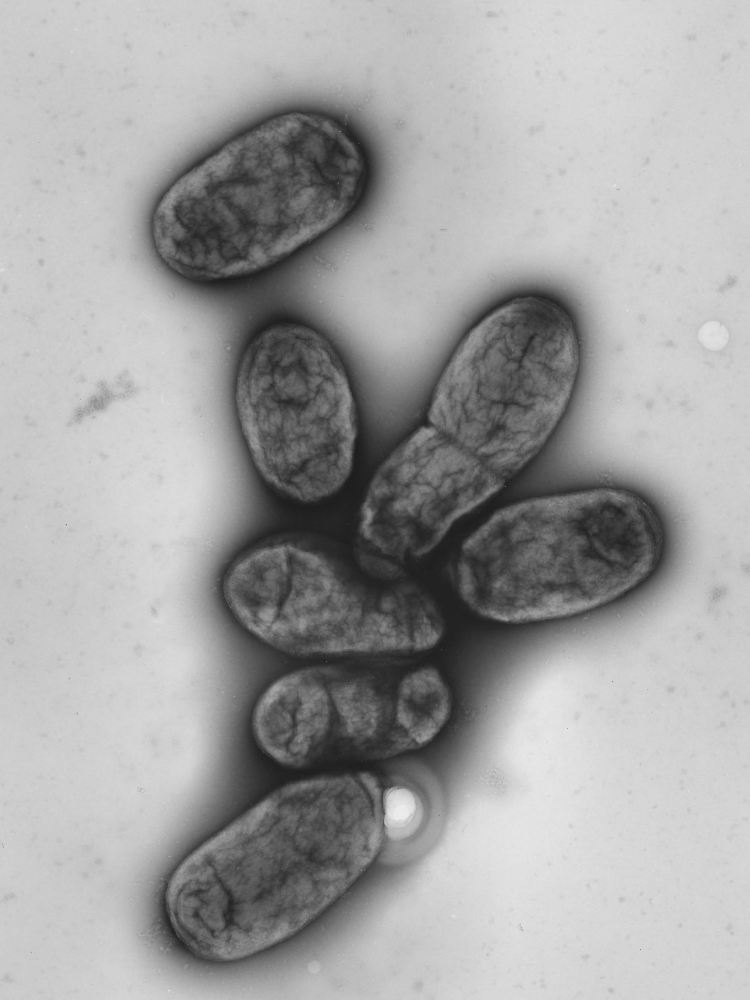

Elektronenmikroskopische Aufnahme des Pestbakteriums Yersinia pestis.

(Foto: Robert-Koch-Institut/dpa)